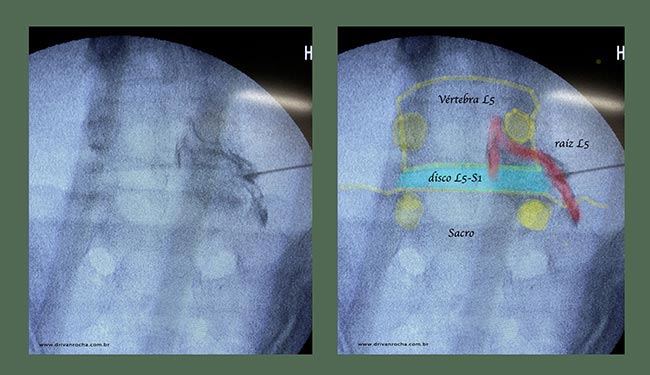

Podemos observar na Figura ao lado um Rx da coluna lombar em que se observa o contraste em preto corando a raiz de L5 a e o saco dural no interior do canal vertebral, isto indica o bom posicionamento da agulha.

Ao lado observamos a mesma figura com suas estruturas anatômicas de referencia em realce. Em amarelo os pontos anatômicos ósseos como o pedículo da vértebra de l5 bilateral e de s1 bilateral, em azul o disco intervertebral L5-S1 e em vermelho as raízes.